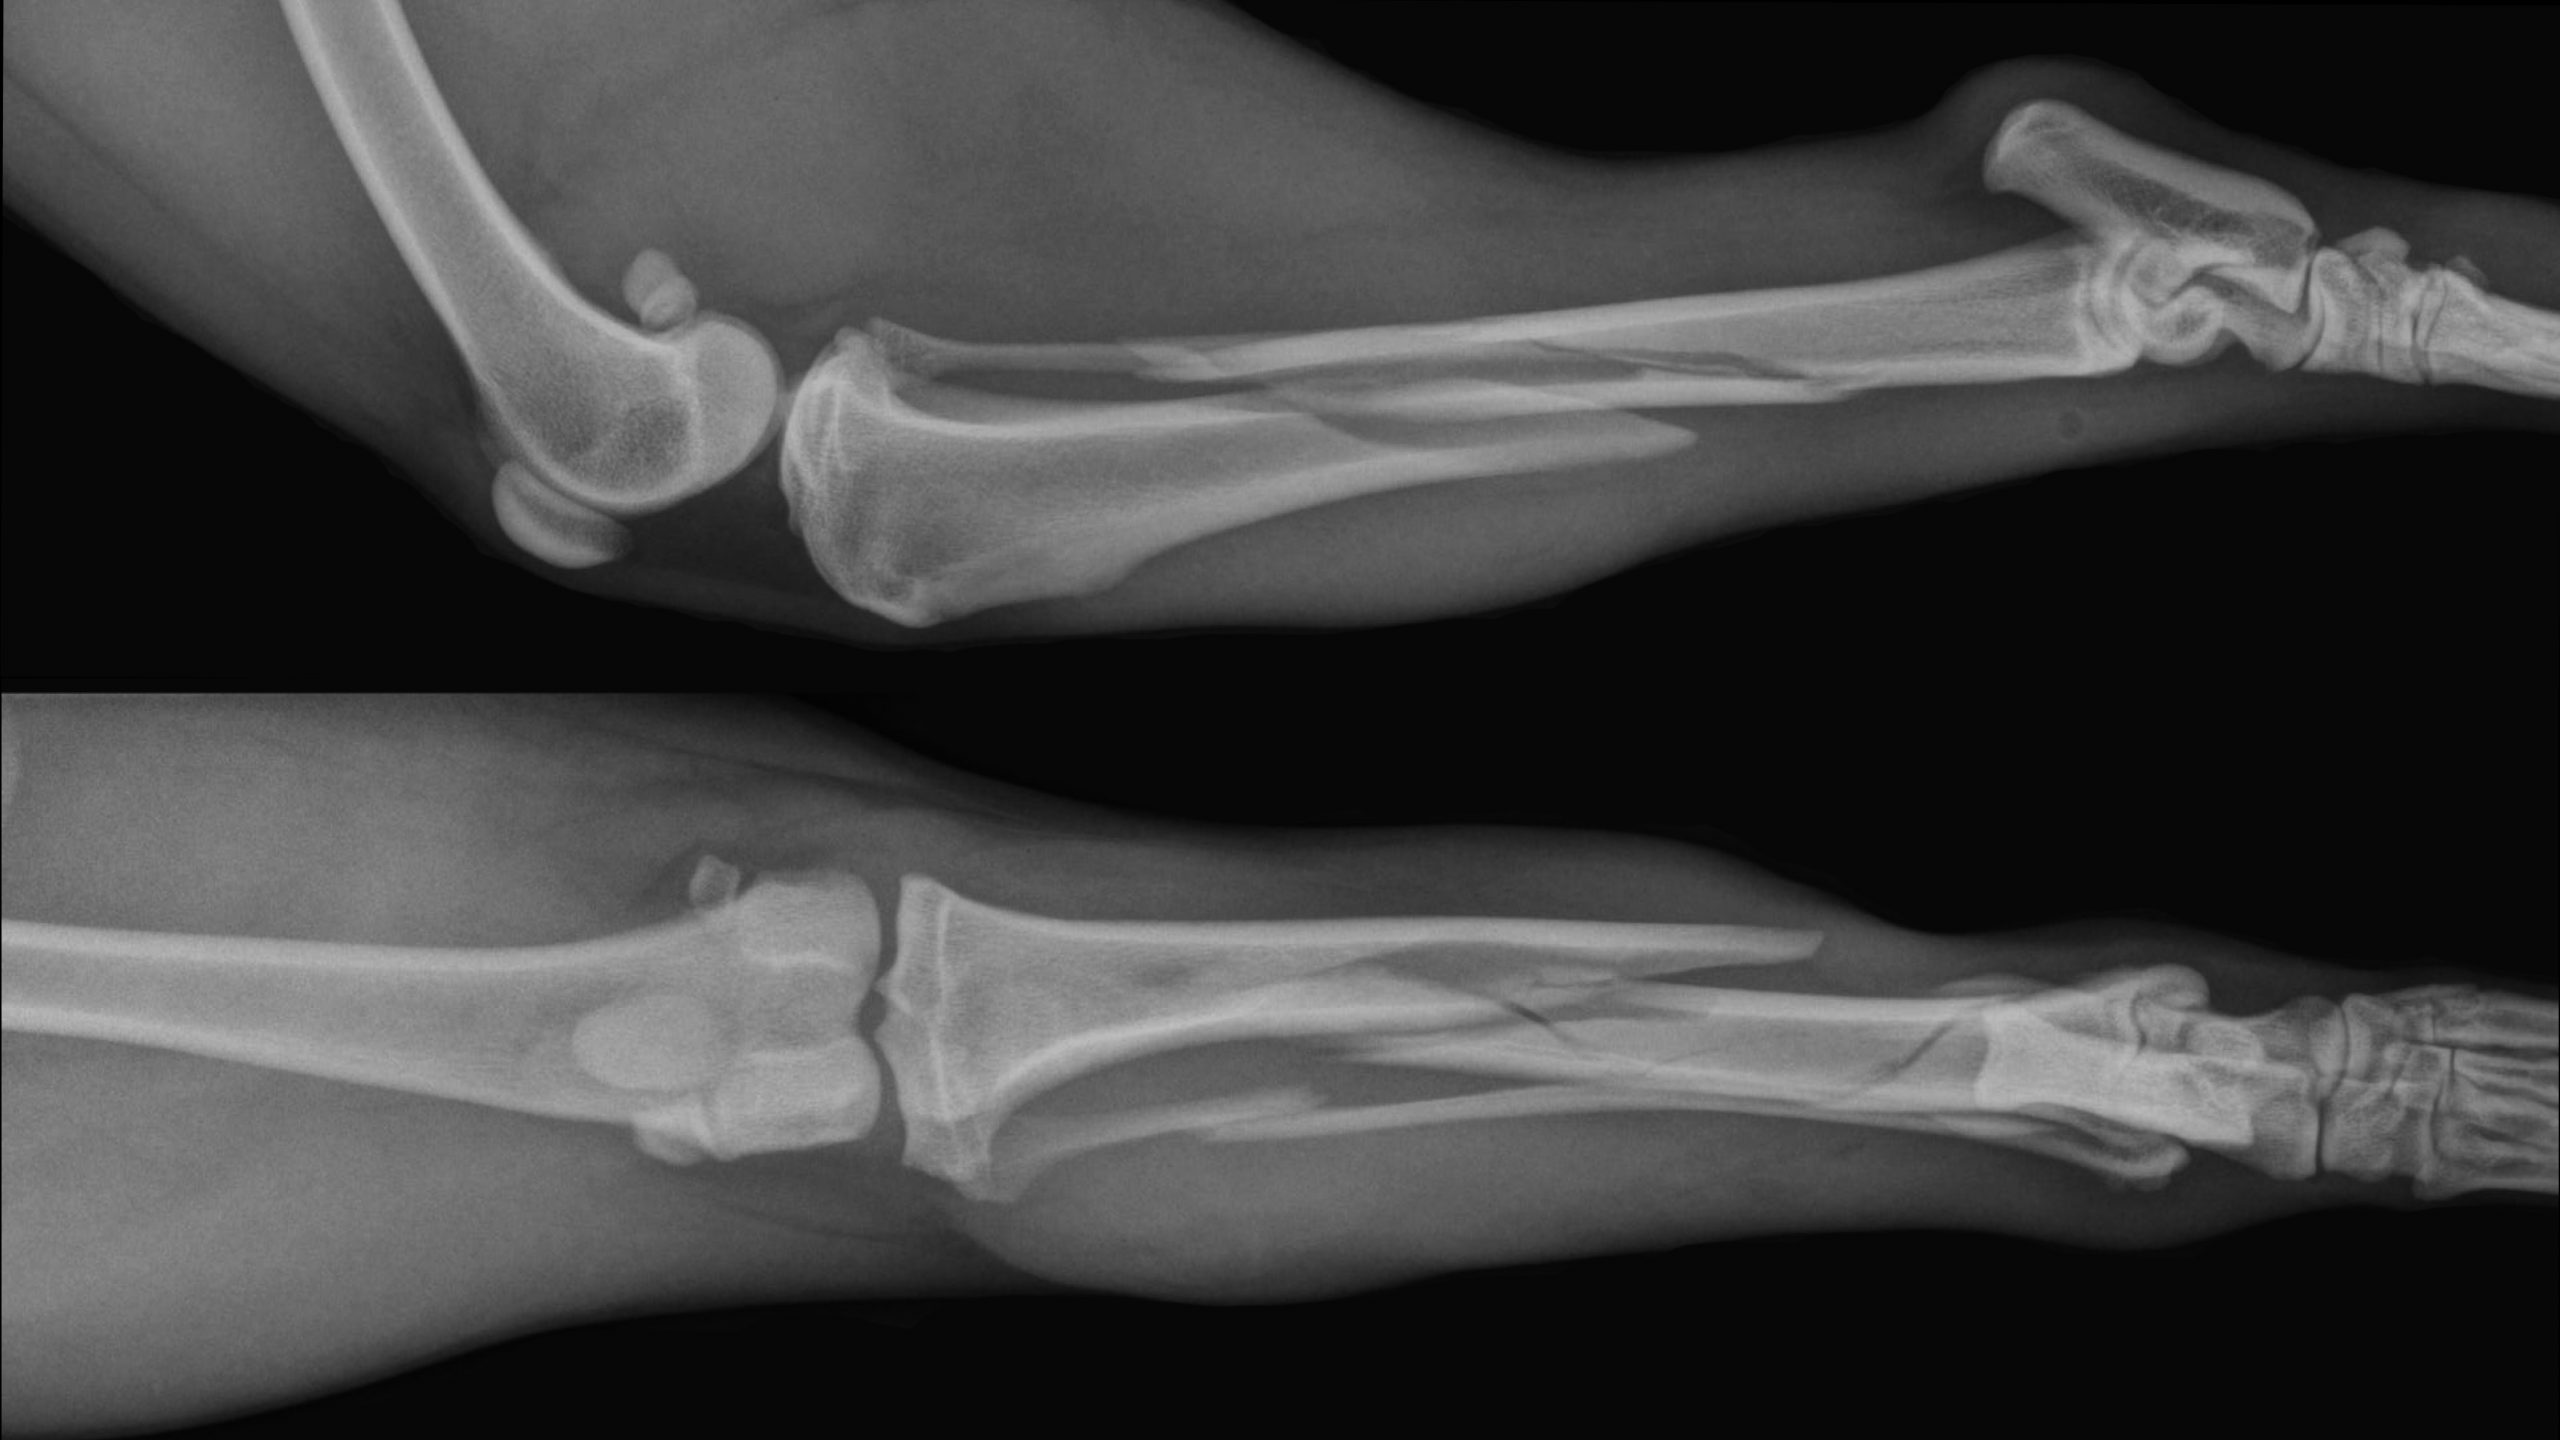

From stock.adobe.com

Dog X Ray. Radius and Ulna Fracture Repair with Plate and Screw in Dog What Happens When A Dog Breaks A Bone If your dog has an accident that causes extreme pain and lameness in one limb, it may be a broken bone. Broken legs are somewhat common injuries in dogs. When a dog breaks a bone, the symptoms will often be. It's important to take appropriate action and check for any serious complications if your dog breaks a bone. If your. What Happens When A Dog Breaks A Bone.